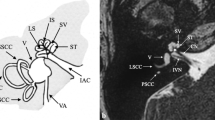

Anatomy of the cochlea and cochlear nerve by high-resolution MR. Heavy T2-weighted driven equilibrium (DRIVE) images in axial (a) and sagittal oblique (b and c) planes. The cochlear turns with internal spiral lamina (arrow) are visible with this high T2-weighted axial image (a). The cochlear nerve (dotted arrow) is seen at the fundus of the IAC (a). With sagittal oblique imaging, the vestibulocochlear nerve (arrow) is seen as a crescent-shaped structure at the medial aspect of the IAC (b); however more laterally the cochlear nerve (arrow) can be seen separately from the inferior and superior vestibular nerves (c)

Radiological assessment with MR not only gives detailed information regarding the inner ear structures but it is also essential for the assessment of the cochlear nerve. The evaluation of the cochleovestibular nerve and especially of its cochlear branch is of extreme importance prior to cochlear implantation. In a normal-sized IAC the diagnosis of cochlear nerve aplasia is relatively straightforward with dedicated sagittal oblique high-resolution images (Fig. 7.5b, c) [36]. However, in a very stenotic IAC, the diagnosis may be difficult because of the inability to separate the nerves [30, 32]. Again the visualized inner ear may be normal or have subtle abnormality despite severe deficiency of the cochlear nerve [12, 36]. Differentiation between hypoplasia and a normal size of the cochlear nerve can also be challenging and requires the highest possible resolution [12]. There is not a well-defined consensus regarding the definition of cochlear nerve hypoplasia. Li et al. defined cochlear nerve hypoplasia as a cochlear nerve with a diameter smaller than that of the facial nerve, seen on the oblique sagittal images. Similarly Glastonbury designated the cochlear nerve as small when it appeared decreased in size compared with the other nerves of the IAC [12]. It is critical to recognize that there might be occasional discrepancy between the imaging and audiological findings regarding the presence/functionality of the cochlear nerve [37, 38]. Several studies have shown that subsets of patients with cochlear nerve aplasia have positive audiological responses and might derive benefit from cochlear implantation [37,38,39]. Anatomical connections between the cochlear nerve and other branches of the vestibulocochlear complex that are below the resolution of the current MR imaging might be responsible for this radiological-audiological inconsistency [40]. Imaging with ultra-high field magnets with DTI fiber tractography might solve this problem in the future [18, 41].